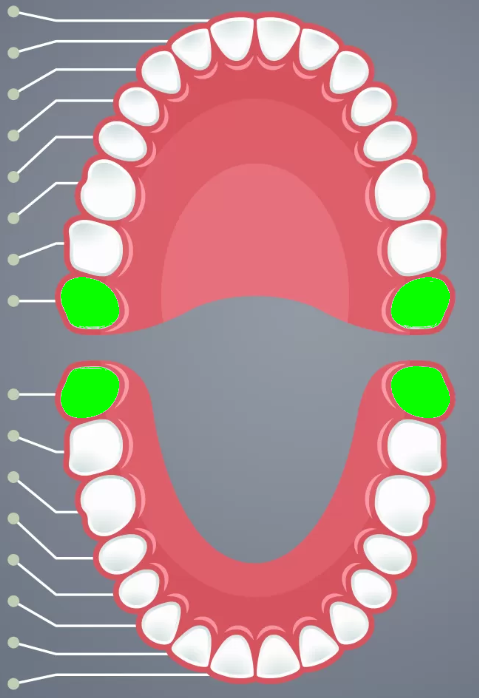

Incisors

Cuspids

Bicuspids

2nd molars

3rd molars